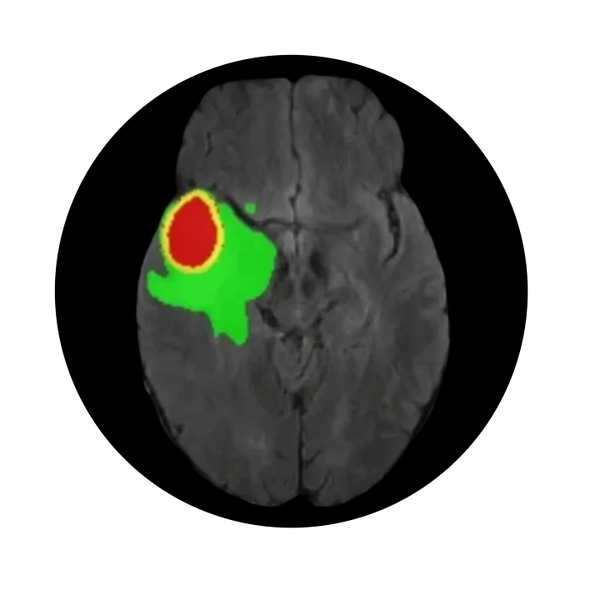

Brain and CNS tumors are one among the most fatal tumor associated with high morbidity and mortality. There are two main types of brain tumors depending upon their origin. Primary brain tumor originates in the brain and CNS region while secondary tumor (metastatic tumor) originates else where in the body and spread to the brain. The most common types primary brain tumors are Gliomas, Meningioma, Medulloblastomas (common in children), Pituitary Adenomas and Schwannomas. Diagnosis and treatment types varies for each type of tumor, depending up on tumor types, location, patient's overall health. Gliomas are the most common type primary brain tumor.

Primary diagnostic procedure involves recording and analyzing multiparametric MRI images which captures different aspects of tumor and provide better resolution for soft tissue without any harmful radiation. Our neuroimaging analytics solutions utilize MRI sequences to diagnose and access clinical conditions. Diagnosis plays a crucial role in treatment planning. This is where we play a critical role in assisting neuroradiologists.

Our solution provides high-precision analytics tools that integrates AI models and advanced algorithms to simplify the landscape of complex brain surgery. During neurosurgery nerve damage is one of the most common causes of neurological deficit which accounts for 41% while 6% (Acta Neurochirurgica, 2020, 162:3005–3018) remains as permanent deficit leading to disability adjusted life years (DALYs) for the patient.